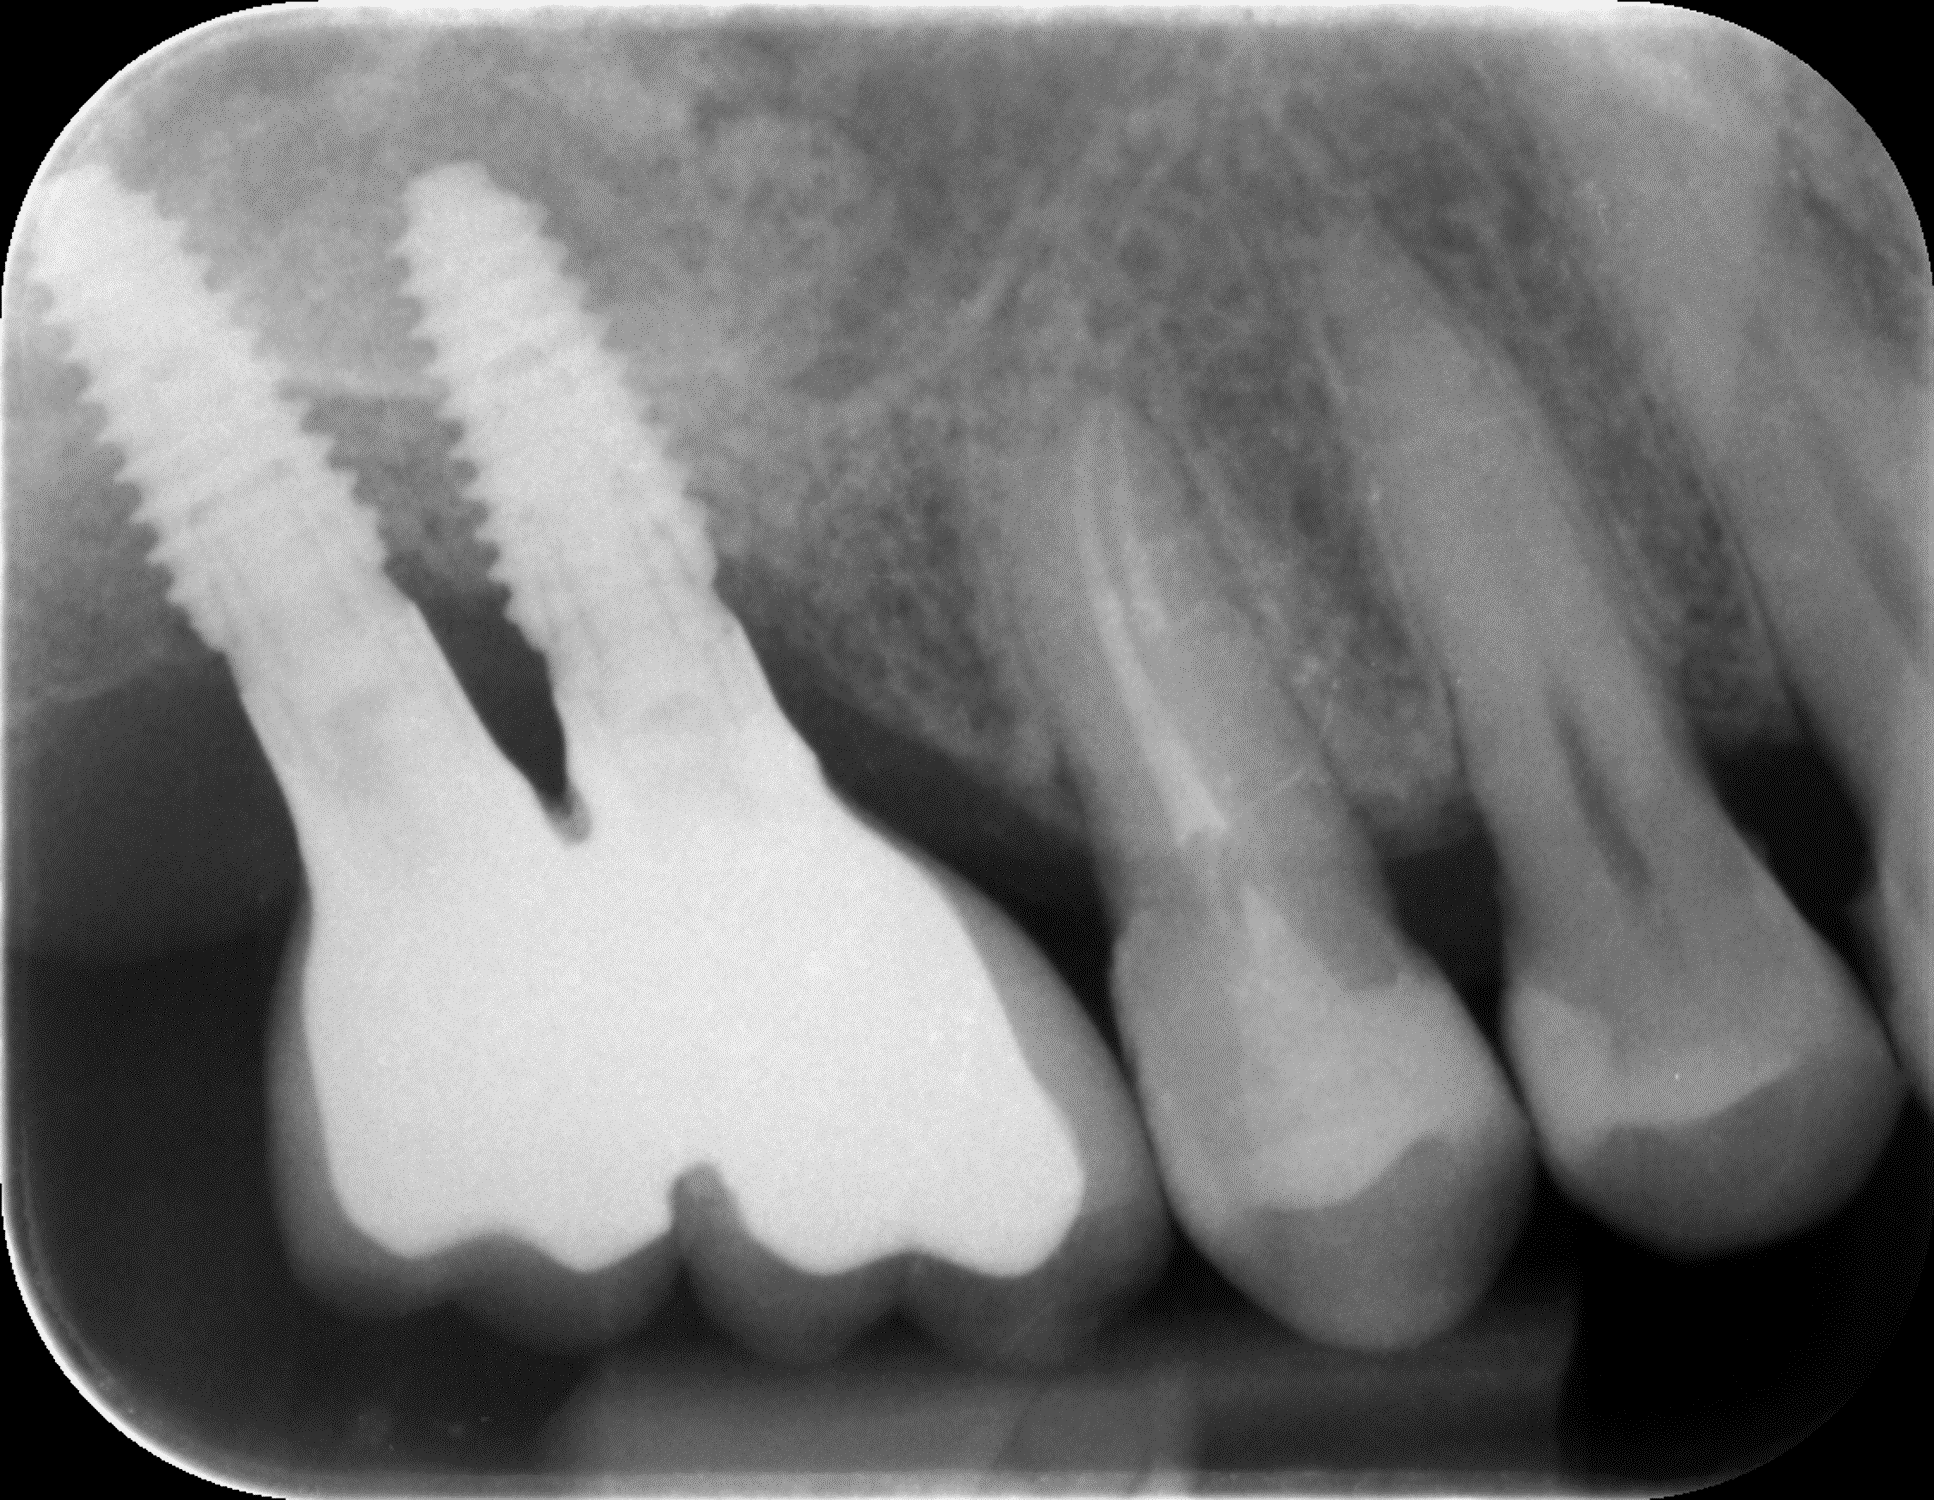

Împreună cu pacientul, am optat pentru inserarea implantelor cu ajutorul ghidului chirurgical pentru a plasa implantul în poziția protetică ideală și pentru a permite realizarea coroanelor insurubate pe implant. A fost efectuată scanarea digitală a arcadelor și a ocluziei pacientului, iar împreună cu tehnicianul radiolog de la DigiRay a fost suprapus fișierul .stl al amprentei digitale peste fișierul .dcm de la CBCT, utilizând software-ul 3Shape.

S-a planificat individual poziția și axul de inserție al fiecărui implant.